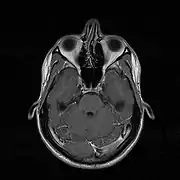

МРТ носової перегородки.

МРТ викривленої носової перегородки